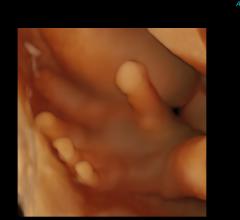

Angiography, Computed Tomography (CT), Flat Panel Displays, Information Technology, Magnetic Resonance Imaging (MRI), Mobile C-Arms, Nuclear Imaging, Ultrasound Imaging

Canon Medical Systems’ offering includes: computed tomography, magnetic resonance, ultrasound, X-ray, cath and EP lab